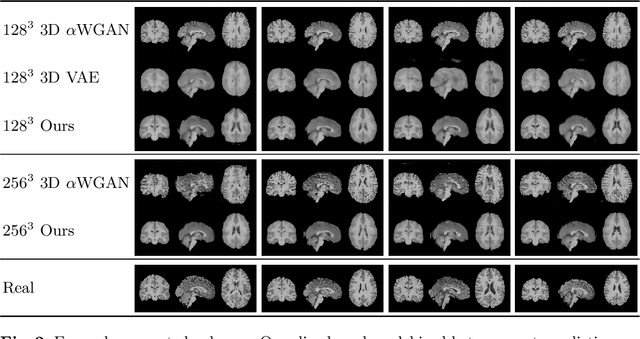

Abstract:Probabilistic modelling has been an essential tool in medical image analysis, especially for analyzing brain Magnetic Resonance Images (MRI). Recent deep learning techniques for estimating high-dimensional distributions, in particular Variational Autoencoders (VAEs), opened up new avenues for probabilistic modeling. Modelling of volumetric data has remained a challenge, however, because constraints on available computation and training data make it difficult effectively leverage VAEs, which are well-developed for 2D images. We propose a method to model 3D MR brain volumes distribution by combining a 2D slice VAE with a Gaussian model that captures the relationships between slices. We do so by estimating the sample mean and covariance in the latent space of the 2D model over the slice direction. This combined model lets us sample new coherent stacks of latent variables to decode into slices of a volume. We also introduce a novel evaluation method for generated volumes that quantifies how well their segmentations match those of true brain anatomy. We demonstrate that our proposed model is competitive in generating high quality volumes at high resolutions according to both traditional metrics and our proposed evaluation.